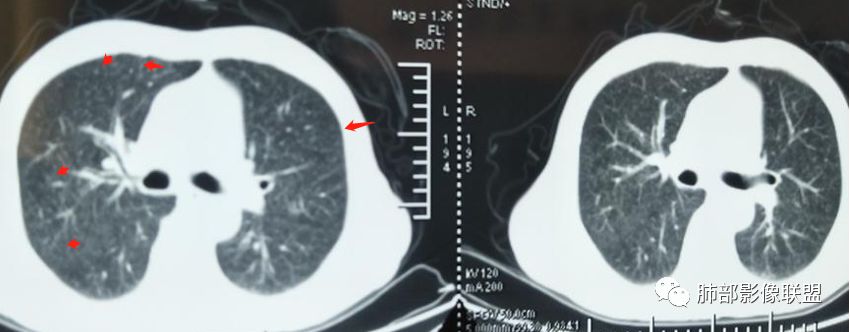

2019-10-20复查CT如下:

两肺弥漫性粟粒样结节伴左上肺小结节,呈三均匀分布,有结核的临床表现,支持血性播散性肺结核。

大小、分布均匀,边缘清楚

细小结节,弥漫,撒米粒样——血道来源

部分可见分支状

血道来源的病灶,均匀、细微,而且部分有分支状,都符合粟粒型肺结核

急性血行播散型肺结核  两肺广泛分布粟粒大小的结节状密度增高影,具有大小均匀、分布均匀、密度均匀的典型“三均匀”特征,注意急性血播病灶非常小,一般粟粒影直径1~2mm。

病灶密集者出现肺外围血管影不清或减少。

发热初期肺部可缺乏典型影像学改变,1到2周后出现的广泛粟粒结节对诊断具有高度提示作用!